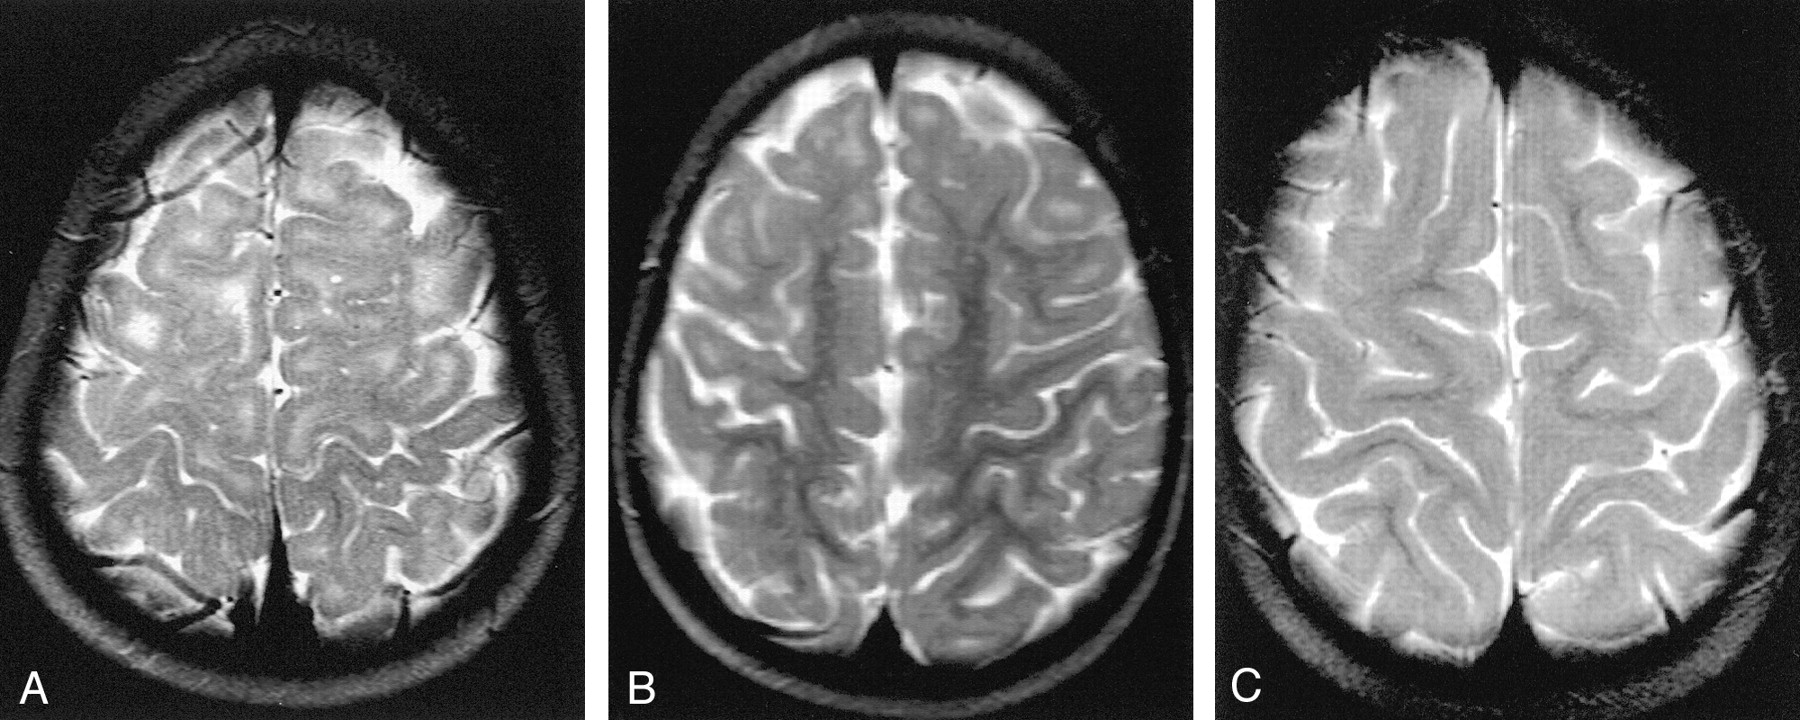

A and B, Axial T2-weighted MR images show grade 0 myelination in the temporal lobe. Subcortical T2 hyperintensity is recognizable in both temporopolar (A) and temporolateral (B) areas.